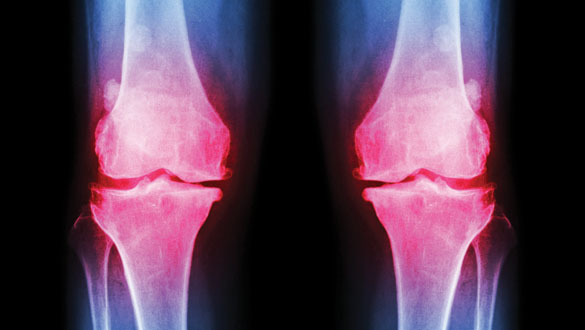

Cases of osteoarthritis of the knee have dramatically increased in prevalence since the mid-twentieth century, which is largely believed to be due to rising obesity rates and people living longer.

The study, published in PNAS, revealed that incidences of osteoarthritis of the knee had, in fact, doubled.

The significance of these findings are that there may be risk factors for osteoarthritis of the knee, aside from increased BMI and longevity, that are not widely documented.